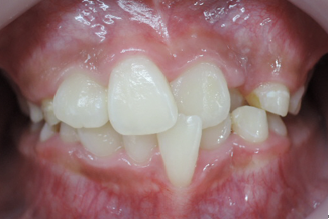

よく診る、難しい症例(奥歯の隙間)